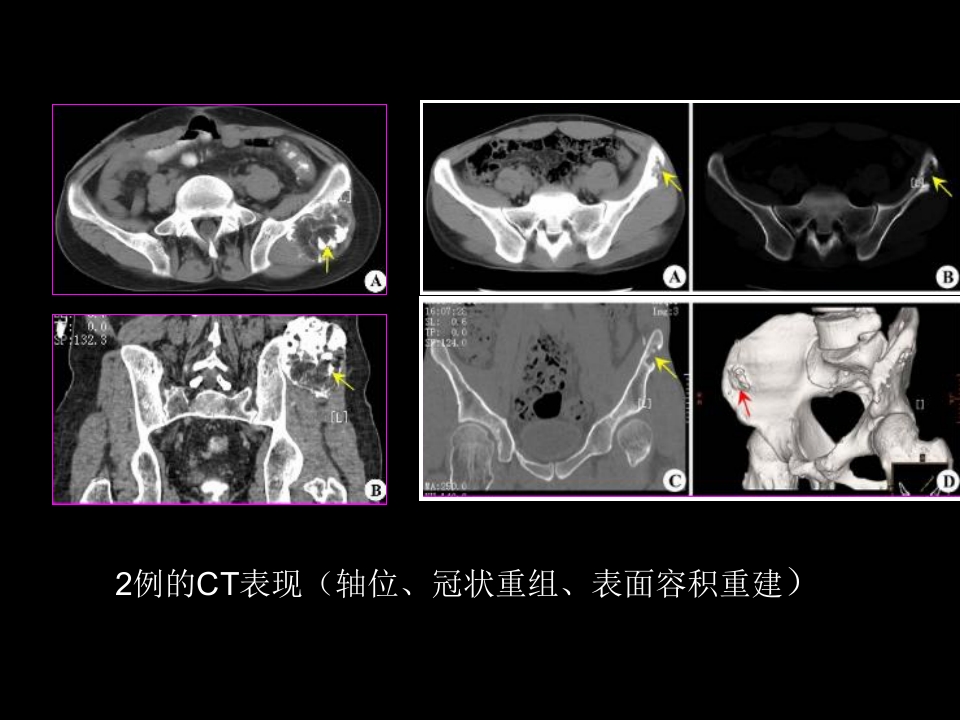

骨肿瘤影像学诊断